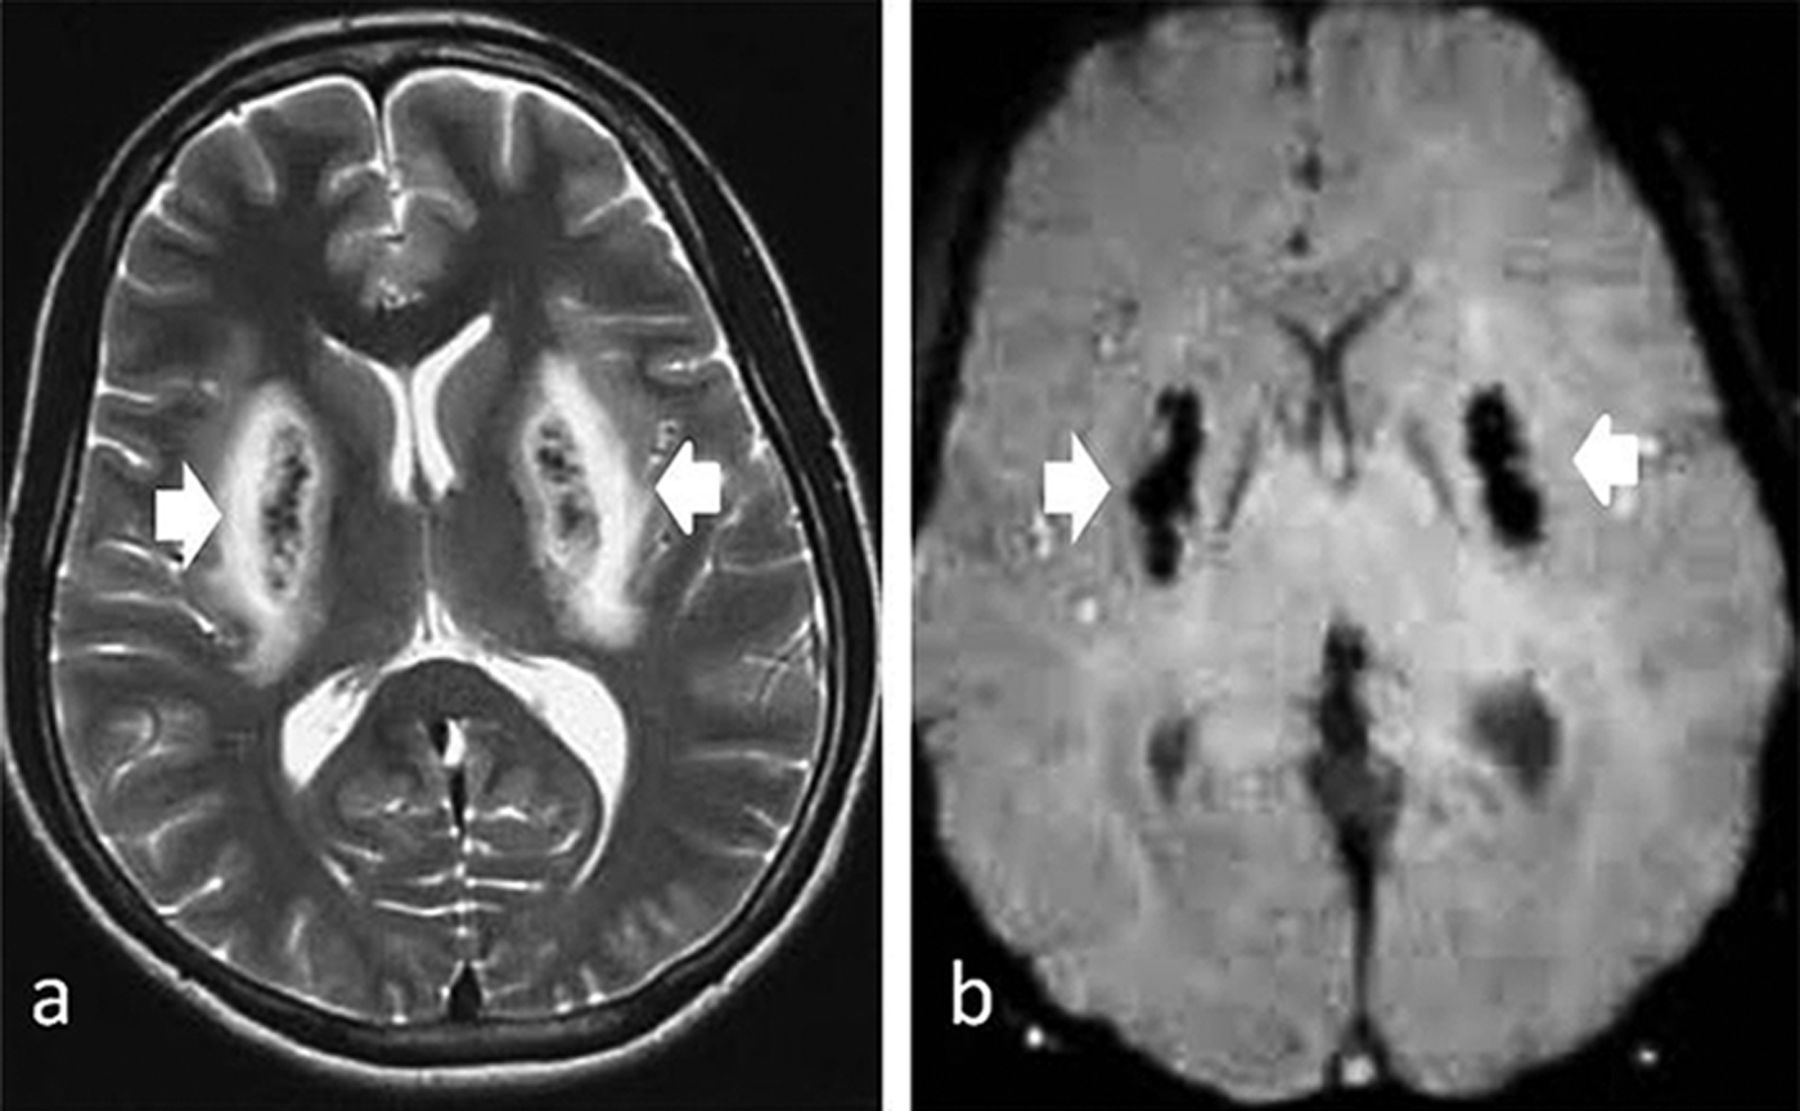

From pn.bmj.com

Methanol toxicity presenting as haemorrhagic putaminal necrosis and Methyl Alcohol Vision Loss Diagnosis of nutritional and toxic optic neuropathies. In our study, all patients experienced bilateral, painless, acute, and dramatic visual loss regardless of the exposure route and the. Formic acid accumulates within the optic nerve, which results in the classic visual symptoms of flashes of. Chronic methanol toxicity can have neurologic sequelae such as vision loss that. Acute optic neuropathy secondary. Methyl Alcohol Vision Loss.

Methanol toxicity presenting as haemorrhagic putaminal necrosis and Methyl Alcohol Vision Loss Acute optic neuropathy secondary to methyl alcohol consumption is a serious ocular disease with permanent vision loss or scotoma. Chronic methanol toxicity can have neurologic sequelae such as vision loss that. A quick treatment based on dialysis, intravenous ethanol, sodium bicarbonate, vitamin b12, and intravenous methylprednisolone slows the. Formic acid accumulates within the optic nerve, which results in the classic. Methyl Alcohol Vision Loss.